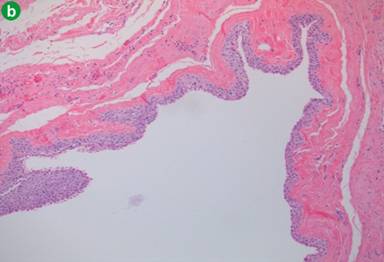

Macroscopically, the cystic lesion of the pancreas (3.0x2.0 cm) was unilocular, with smooth internal and external surfaces and contained serous clear fluid. Histological examination of the pancreatic parenchyma section revealed the presence of a dilated main pancreatic duct and a cyst with a fibrous wall. The cyst was lined by multilayered epithelium, without cytological atypias. It was surrounded by normal pancreatic parenchyma and by fat tissue, without any signs of pancreatitis. No tall columnar mucinous cells were identified. No associated lymphoid or splenic tissues were present. The lesion did not display ovarianlike stroma (Figure 2ab). The epithelium of the cyst reacted positively with cytokeratin 7 (CK 7, expression profile of pancreatic ducts), but negatively with CK 5 in immunohistochemistry.

Figure 2. Squamoid cyst of pancreatic ducts is lined by non-keratinized squamous epithelium (hematoxylin-eosin stain; a. 5x; b. 10x). |